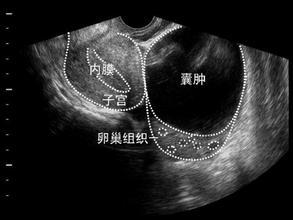

卵巢囊肿

卵巢囊肿,不是一个独立的疾病的名称,是很多疾病的一个共同的超声表现,大约5%的恶性率,因此医生也非常重视。是否治疗、是否手术,我们应该听从医生的建议。